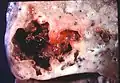

Lung abscess is a type of liquefactive necrosis of the lung tissue and formation of cavities (more than 2 cm)[1] containing necrotic debris or fluid caused by microbial infection.

This pus-filled cavity is often caused by aspiration, which may occur during anesthesia, sedation, or unconsciousness from injury. Alcoholism is the most common condition predisposing to lung abscesses.